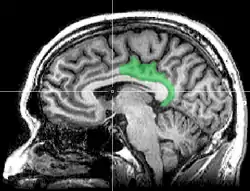

![]() Sagittal MRI slice with highlighting indicating location of the posterior cingulate | |